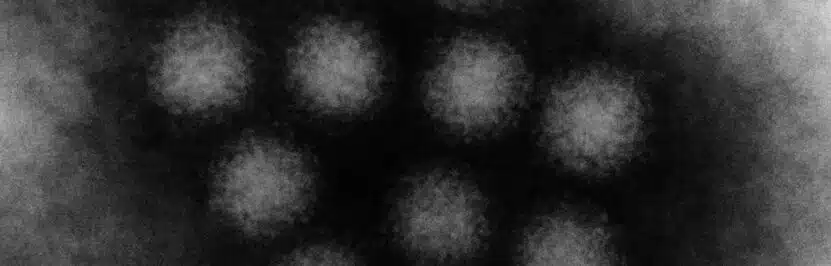

Noroviry jsou neobalené jednovláknové RNA-viry, které způsobují epidemickou akutní gastroenteritidu. Noroviry patří do čeledi Caliciviridae.